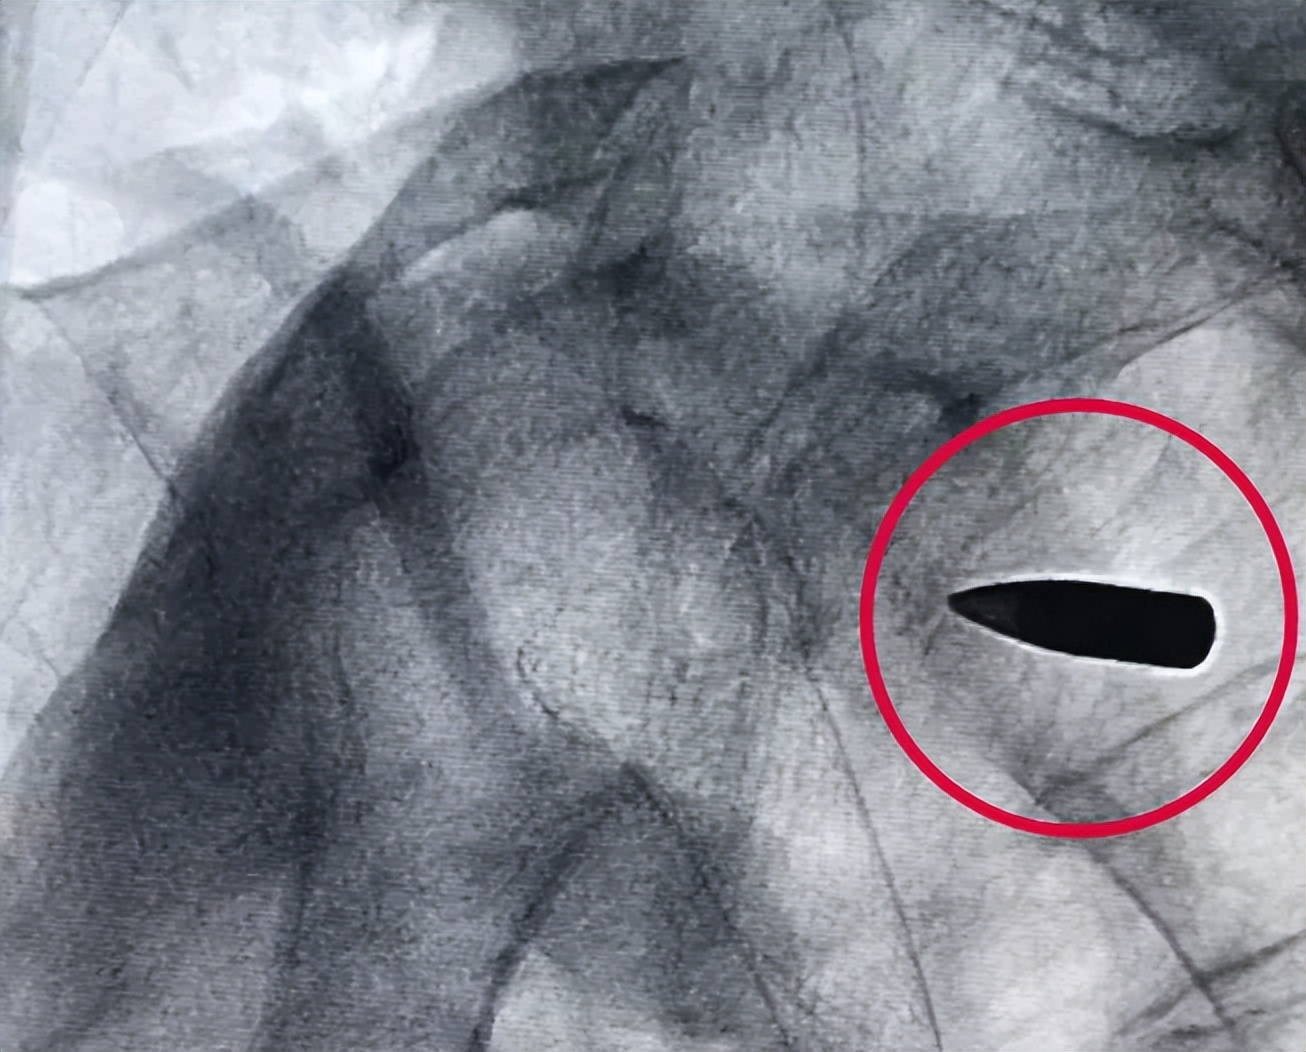

爆料三:一颗藏在体内七十多年的*弹子**?

近日,97岁抗美援朝老战士罗锦文因吞咽困难无法正常饮食而前往浙江省平湖市第一人民医院就医,扫描结果发现一颗藏在体内70多年的*弹子**。老战士说1949年自己在战斗中被流弹打中,当时检查伤口并未摸到*弹子**,仅仅简单包扎后又继续投入战斗,2012年身体不适就医时第一次知道自己体内留有一颗*弹子**。经医院全方面检查,考虑到*弹子**对老战士的日常生活影响不大,家属决定不予取出。目前,老战士罗锦文已完成食道支架手术,正在医院静养。